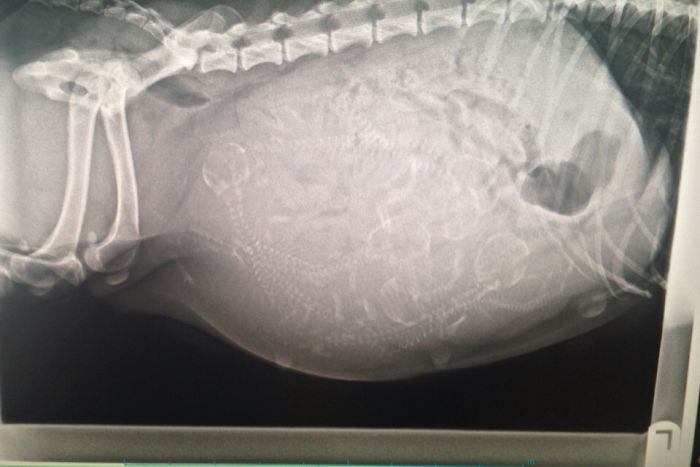

X-Ray Of A Pregnant Dog